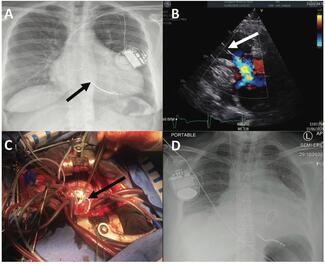

Daniel Garner, MBChB; Goutham Meda; Keyomi Gunarathne Mudiyansege, MBChB; Victoria Pettemerides, MBBS, BSc, MRCP; Mark Pullan, FRCS; Archana Rao, MD, MB, MRCP, MBBS

Dr. Garner and colleagues present a case of severe symptomatic TR due to right ventricular leads, in a patient with hypertrophic cardiomyopathy and concomitant left ventricular outflow tract obstruction with mitral valve regurgitation.